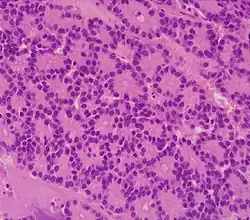

| Micrograph of an acinar cell carcinoma of the pancreas. H&E stain. | |

Histomorphologically, the tumour resembles the cells of the pancreatic acini and, typically, have moderate granular cytoplasm that stain with both PAS and PASD.[4]

Light microscopy of an acinar cell carcinoma biopsy typically shows granular appearance.[6] Immunohistochemistry is usually positive for trypsin, chymotrypsin and lipase.[6] On genetic testing, altered genes/proteins are typically found for p53, SMAD4, APC, ARID1A and GNAS.[6]